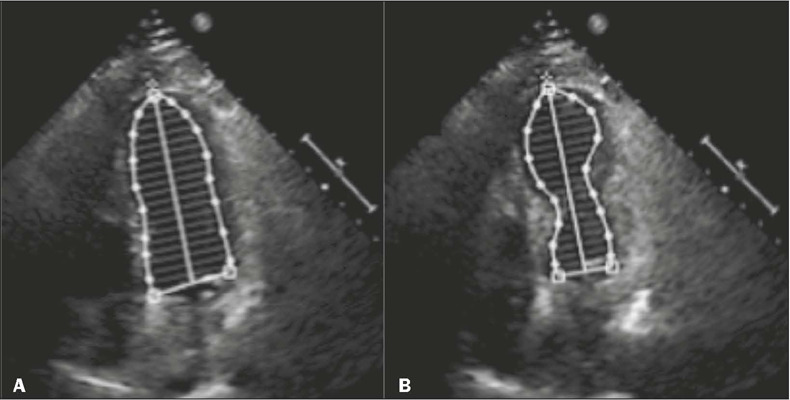

Takotsubo cardiomyopathy is an important differential diagnosis for acute chest pain. Imaging tests, such as ventriculography, echocardiography, computed tomography of the heart, and cardiac magnetic resonance, are valuable tools for diagnostic confirmation in this context. This study reviews the literature and exemplifies the spectrum of typical and atypical cardiac magnetic resonance findings in this disease, on the basis of the experience of our facility. Recognition of these characteristics underscores the roles that radiologists and cardiologists play in the care of patients with acute chest pain, enabling an accurate diagnosis and appropriate treatment.